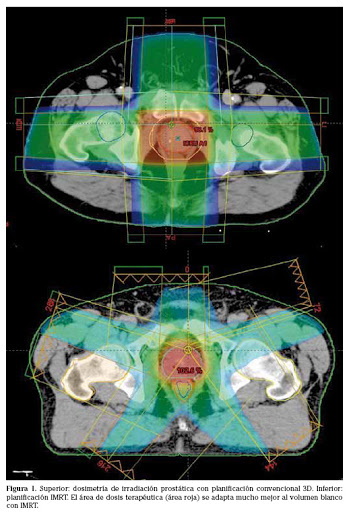

La radioterapia de la última década, junto con los avances tecnológicos que esto conlleva, ha logrado disminuir en forma importante las complicaciones de toxicidad en los tejidos vecinos, en los tratamientos oncológicos de casi todas las patologías. En uro-oncología, es un tratamiento standard para algunas patologías en su tratamiento definitivo, adyudante y/o metastásico. La disminución de la toxicidad aguda y tardía ha ocurrido con la expansión del uso de la Radioterapia de intensidad modulada (IMRT), la radioterapia guiada por imágenes (IGRT) y la braquiterapia de alta tasa de dosis. Es por esto que su uso ha ido en aumento en algunas patologías con intención curativa y paliativa, tanto en cáncer de próstata, tratamientos en preservación de órgano (Cáncer de vejiga) y en pacientes oligometastásicos.

Se presentan figuras de un caso clínico de nuestro centro. Paciente de 57 años, APE: 6.5, Biopsia Gleason 7 (3+4) 2/6 sextantes. Etapificación (-), Rechaza cirugía.